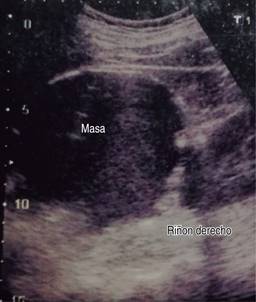

Ultrasonido de marzo reporta hígado de tamaño, forma y situación normales con borde inferior derecho irregular, de ecogenicidad heterogénea por presencia de una masa anecoica de forma redondeada y con bordes bien delimitados, paredes delgadas; sugestivo de quiste simple (Figuras 1 y 2).

Figura 1: Ultrasonido hepático con imagen anecoica redondeada y de paredes delgadas bien delimitadas.